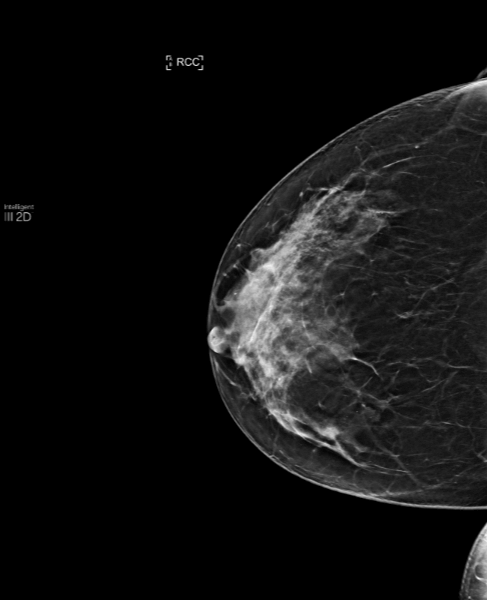

Routine screening on patient.

MammoScreen identifies multiple lesions as a yellow score of 5 (undetermined).

However, the mass of score 5 of the right breast detected on both CC and MLO corresponds to a small infiltrating cancer. Thanks to tomosynthesis, MammoScreen was able to identify this lesion, in particular thanks to slice number 16 of the CC.

Thanks to the yellow score, MammoScreen can draw attention to subtle lesions that can in some cases be malignant.